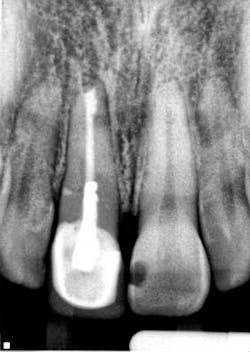

By Manish Garala, BDS, MSEndodontic surgery: an outdated clinical procedure? Endodontic surgery has developed the perception in some areas of dentistry as being an unpredictable and unnecessary procedure, especially with the advent of modern day implants. This opinion has been based on endodontic surgery being performed using outdated concepts and techniques that compromised the potential for clinical success, often resulting in the persistence of patient symptoms, periapical pathology, and, ultimately, extraction of the treated tooth (Fig. 1).

Fig. 1: Radiograph of a failing surgically treated endodontic case. The establishment of new surgical principles based on the use of enhanced magnification and illumination from the surgical operating microscope have addressed the technical and biological deficiencies that were previous barriers to successful, predictable surgical treatment.1 The term microsurgical endodontics has now become synonymous with improved clinical success rates for endodontic surgical procedures, and scientific research has confirmed the merit of this procedure as more than just a last-ditch heroic attempt at tooth retention. Success rates of 90% and above have been reported from prospective case series and randomized controlled trials performed with contemporary techniques and protocols.2,3 The emphasis on using magnification for the identification of apical canal anatomy (Fig. 2), including additional canals, isthmuses, canal fins, and lateral canals (Fig. 3), apical disinfection of the root canal system, and the establishment of an impervious apical seal using biologically acceptable root filling materials such as MTA (Mineral Trioxide Aggregate, Dentsply Tulsa, OK) has enabled the routine achievement of these significantly improved success rates (Figs. 4 and 5).

Fig. 4: Endodontic surgery performed without adhering to contemporary microsurgical principles. An apical seal is not evident and apical pathology has developed radiographically with associated swelling and symptoms.